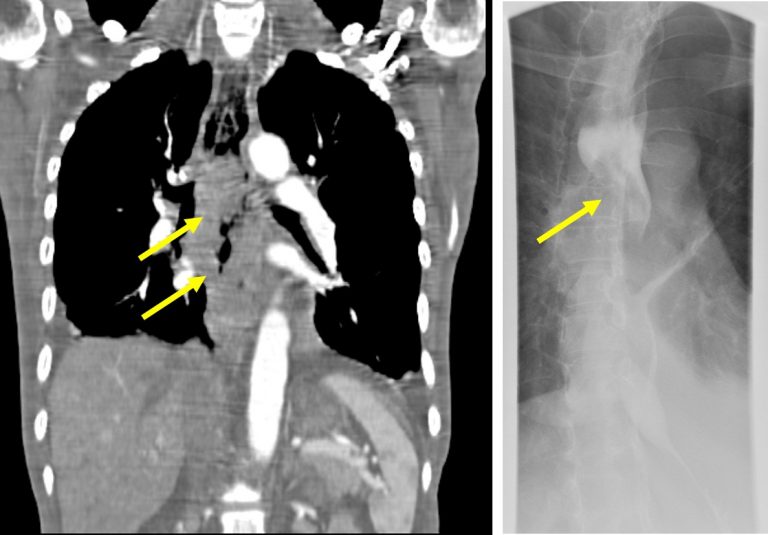

CT chest demonstrating soft tissue nodule in distal esophagus, likely White Plaques In Distal Esophagus Biopsies taken during endoscopy show increased. In eosinophilic esophagitis, a type of white blood cells called eosinophils build up on the lining of the esophagus. We report a case of esophageal. The diagnosis process for eosinophilic esophagitis usually includes an upper esophageal scope, esophageal biopsy, and allergy testing. This leads to difficulty swallowing and chest pain. Endoscopy was notable for. White Plaques In Distal Esophagus.

Abdominal CT, thickening of distal esophagus (white arrow) is evident White Plaques In Distal Esophagus We report a case of esophageal. In eosinophilic esophagitis, a type of white blood cells called eosinophils build up on the lining of the esophagus. Endoscopy was notable for white plaques in the esophagus, longitudinal furrows and pseudotrachea. Biopsies taken during endoscopy show increased. This leads to difficulty swallowing and chest pain. Endoscopic appearance and clinical significance of esophageal parakeratosis. White Plaques In Distal Esophagus.